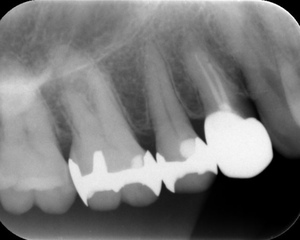

BEFORE

AFTER

基本情報

| 年齢・ 性別 |

31歳・女性 |

|---|---|

| 主訴 | 左下が欠けて穴が空いた 左下6番 |

| 治療 内容 |

左下6番根管治療 |

| 治療 期間 |

約1ヶ月 |

| 治療費 | 来院回数4回 約4,000円(保険診療3割負担) 別途CT代約4,000円(保険診療3割負担) (2024年11月現在) |

| リスク・副作用 | ・神経の治療の刺激により、数日痛み・腫れがでる可能性があります。 ・細く繊細な器具を使用するため、器具が破折する可能性があります。 ・複雑な神経の治療では、大学病院もしくは専門医による治療が必要となることがあります。 ・または抜歯になることもあります。 |

| 治療方針 | 左下6番の歯に穴があき、虫歯が進行していたため根管治療となりました。 |

| 特記事項 | 根が4本あるためCTを撮影し根の形を詳しく確認したところ、そのうちの2本が途中で癒合し根が細くなっていました。 根管が細く癒合もあるため、細く曲がった歯の神経の治療に対応できる弾力が高く柔軟性のあるニッケルチタンファイルを使用。 またラバーダムを用い防湿を行いながら治療を進めました。 |

| 担当者所見 | 今後コア(土台)を入れ被せ物をセットし治療終了となります。 また、引き続き他の虫歯治療を進めていきます。 |